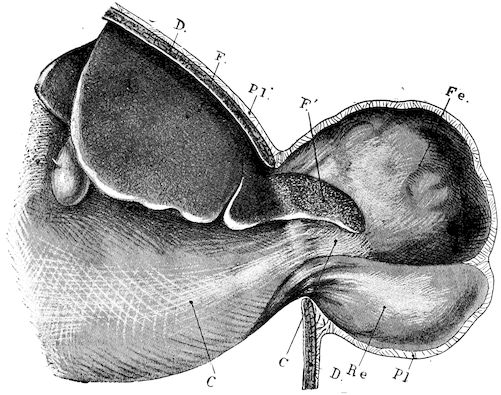

Fig. 10.—Dressing for fracture of the horn.